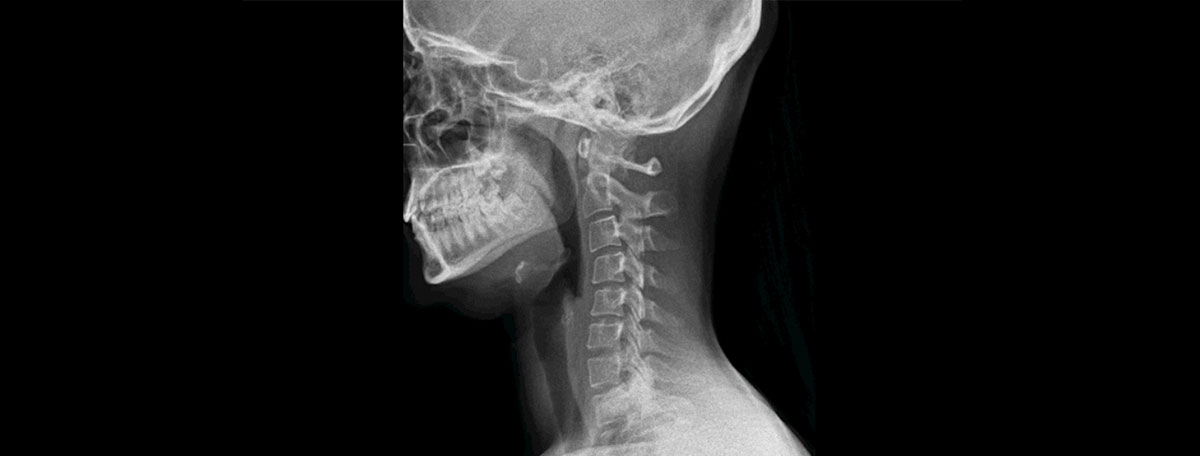

The most advanced medical technology at the service of patients. Our professionals and technical equipment are at the forefront of progress. A new era of health.

Technical development and the continuous training of our professionals are primarily aimed at achieving greater safety in procedures, as well as better outcomes.